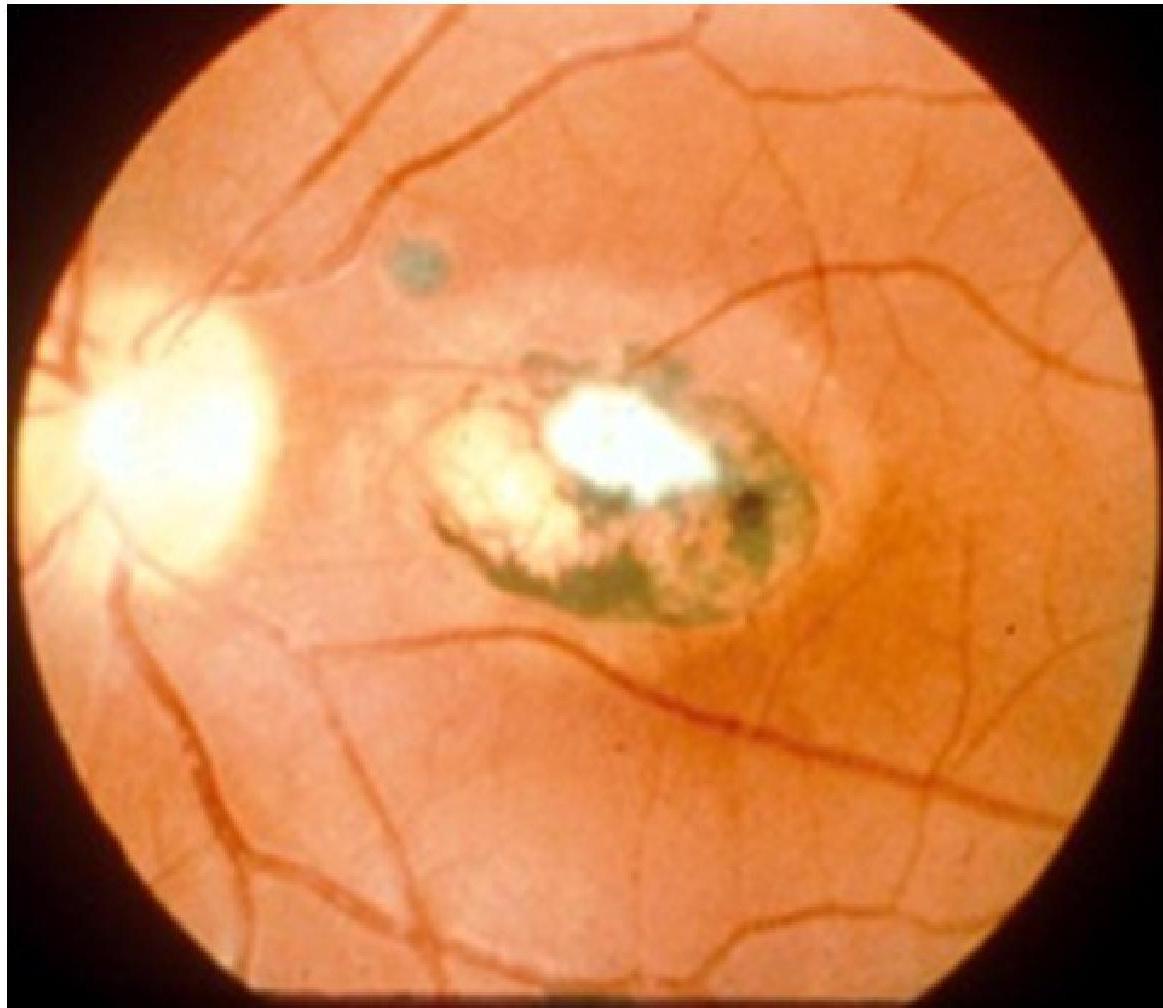

- Chorioretinitis.

Visual Evidence - Chorioretinitis of congenital toxoplasmosis

Congenital Toxoplasmosis

- Initially asymptomatic infants are still at high risk of developing abnormalities especially chorioretinitis.